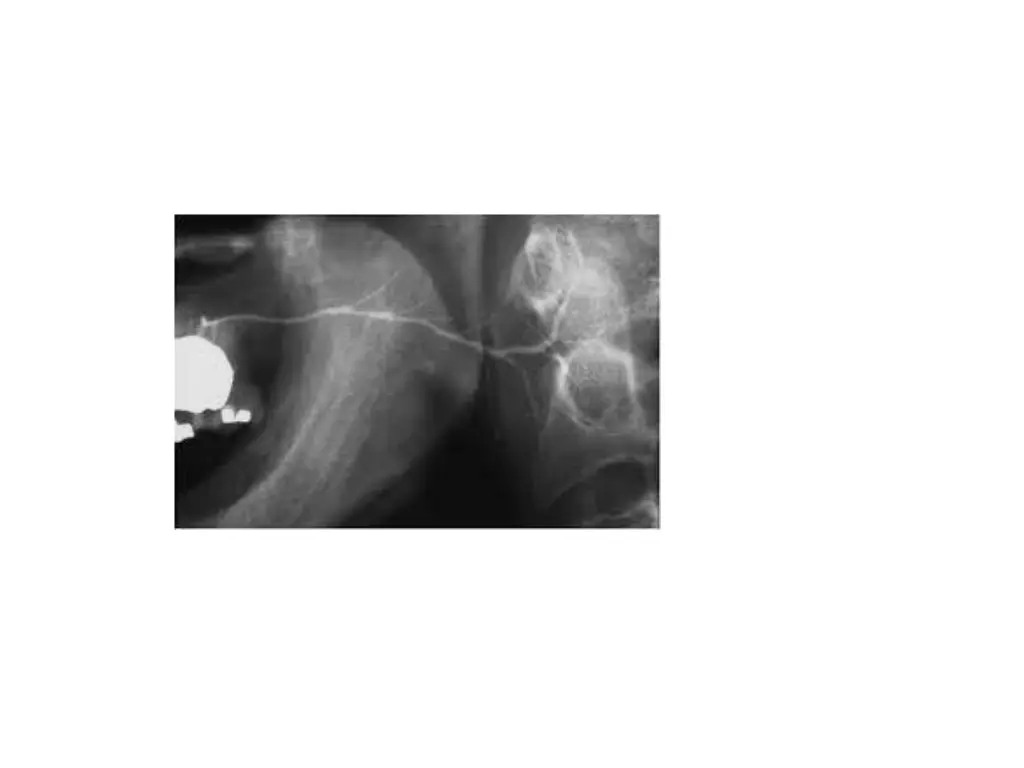

Autoimmune sialadenitis Sialography is helpful in diagnosis and staging of AI disorders Early stages initiation of punctate, less than 1mm and globular, 1-2mm spherical collections of contrast agent evenly distributed throughout the glands These collections are called as sialectases At this stage, main duct appear to be normal but intraglandulr ducts may be narrowed or not even evident

Sialectasia typically remains after the administration of a sialogogue which indicates that contrast agent is pooled extraductally As disease progresses, collections of contrast agent increase in size, greater than 2mm in diameter and irregular in shape These pools of contrast agent are called cavitary sialectases These larger sialectases are fewer in no and less uniformly distributed throughout the glands

Progressive larger cavities of contrast agent and dilation of main ductal system may also be present At endpoint, complete destruction of gland occurs Cavitation and glandular fibrosis are result of recurrent inflammation